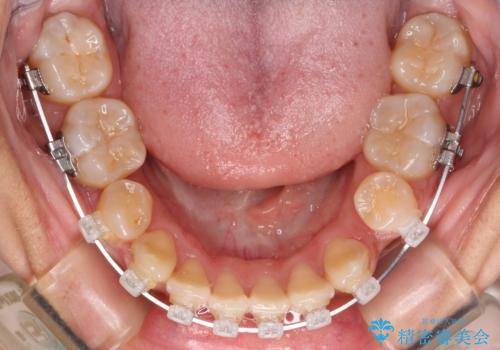

- クリアブラケット

また、開咬を改善するため臼歯部にアンカースクリューを用いて圧下する力をかけていきました。

舌を突出する癖があり、それにより開咬が悪化したり、後戻りの原因になるため、舌のトレーニング(MFT)も行いました。